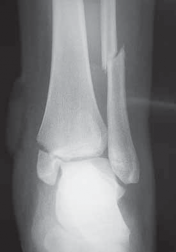

A B C FIG 3•

Radiographic evaluation with an ankle trauma series: AP (

A

), lateral (

B

), and mortise (

C

) views.